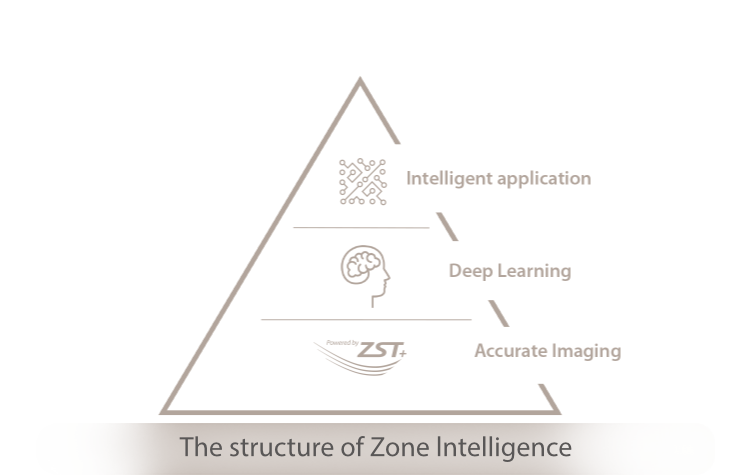

Forwarding Smart to Clinical Intelligence

Powered by the channel data based ZST + platform, the Nuewa R9 with Zone Intelligence 2.0 builds up a truly smart mechanism to deliver a new level of Intelligence.

Forwarding Smart to

Clinical Intelligence

Powered by the channel data based ZST + platform, the Nuewa R9 with Zone Intelligence 2.0 builds up a truly smart mechanism to deliver a new level of Intelligence.